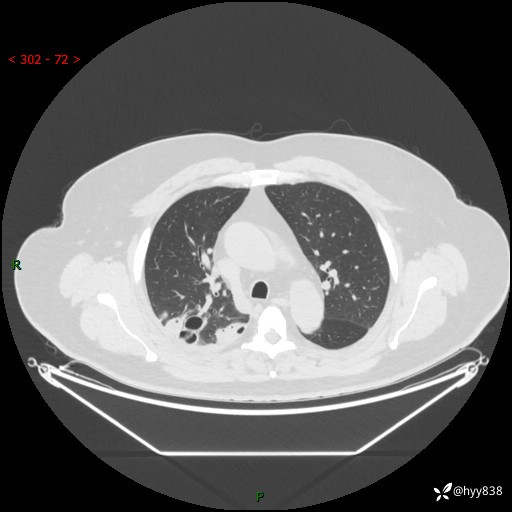

性别:男

年龄:48岁

简要病史:发热来诊(门诊病人)

胸部CT平扫